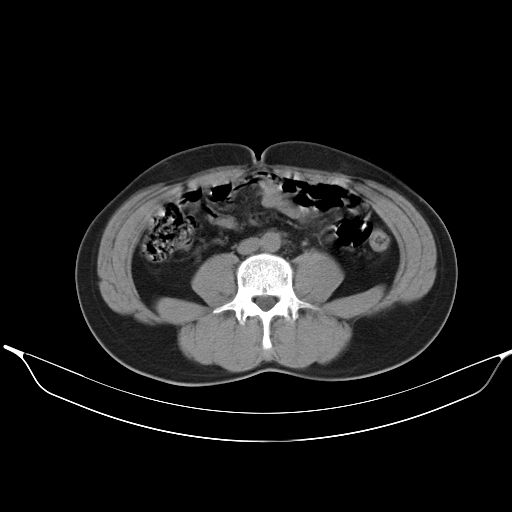

标题: CT25490:男,40岁,体检发现;无其它不适。 [打印本页]

标题: CT25490:男,40岁,体检发现;无其它不适。

转移性肺肿瘤不排除,建议结合相关检查考虑

1、均为转移,原发灶不在肺内。2、肺癌肺转移。